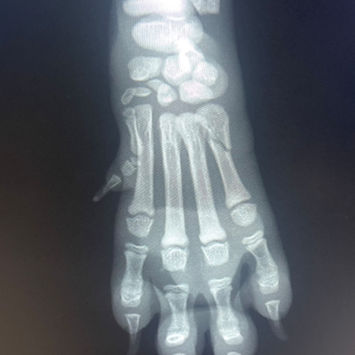

Røntgen

Vi har heldigitalt direkterøntgen på klinikken. Apparatet er helt nytt, og gir oss bilder av svært god kvalitet. Med en gang bildet tas, kommer det opp på skjermen, og vi kan justere posisjon og eksponering ved behov. Dette er et viktig hjelpemiddel i diagnostikken. Vi kan for eksempel se om dyret har beinbrudd eller forkalkninger i skjelettet, man kan se etter svulster i buk og brysthule, og man kan oppdage de fleste former for urinstein. Det brukes også i utredningen av oppkast for å se etter fremmedlegeme i buken. For å sikre oss bilder av god kvalitet, og for at vi som tar bildene, ikke skal bli eksponert for røntgenstråler hver dag, får dyrene litt beroligende før røntgen. Selv små bevegelser hos dyret gjør detaljene i bildet mer uklare. Dersom undersøkelsen før røntgen avdekker forhold som tilsier at beroligende ikke er tilrådelig, f. eks pusteproblemer, så vil bildene tas uten dette.

I tillegg gjøres rutineundersøkelser for å se om dyret lider av arvelig skjelettsykdom som HD, AD og spondylose.